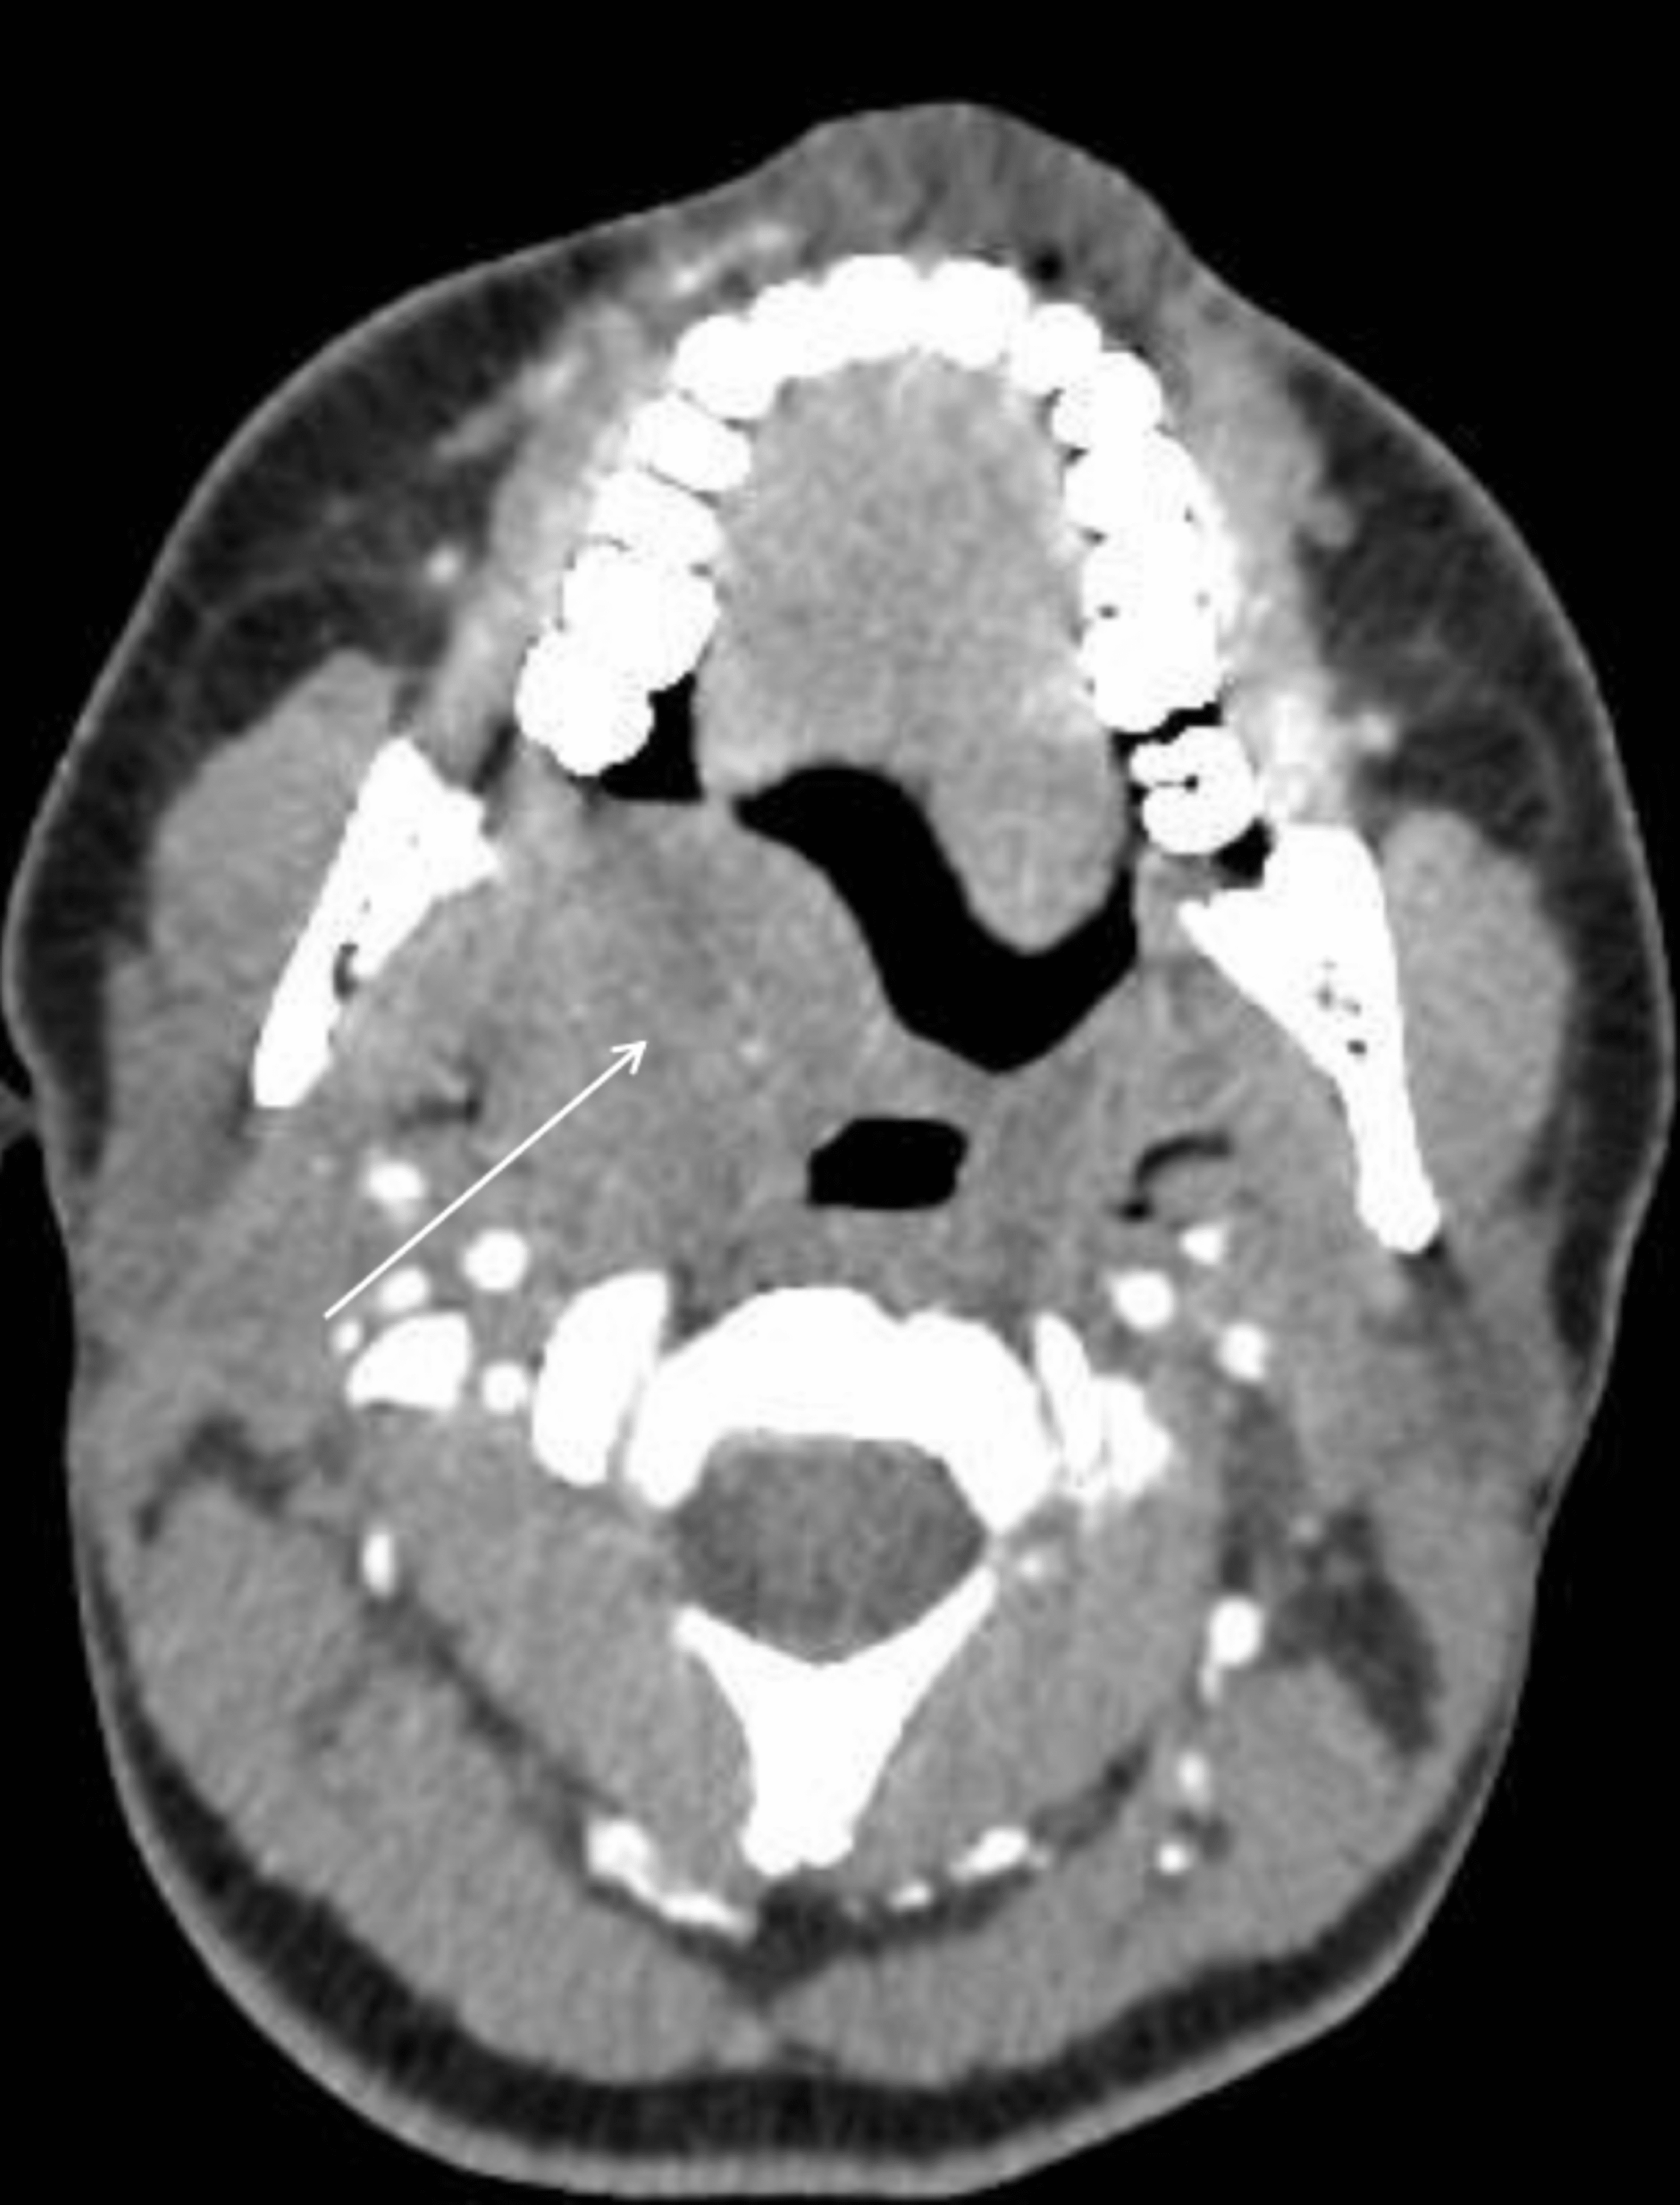

(a) 21 × 24 × 25 mm mass involving the soft palate significantly What Is Palate Mass palatal malignancies are most commonly present as a palatal mass with or without oral bleeding and pain. It separates the oral cavity from the nasal. A mass is any lump in the body that can be caused by the abnormal growth of cells, a. the palate (also known as the ‘roof of the mouth’), forms a division between. What Is Palate Mass.